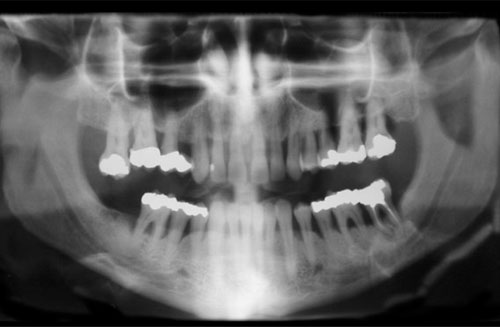

Allvarlig tandlossning

Ofta får man inga symptom på parodontit, förutom att tanden känns lös, men risken för infektion, svullnad och varbildning är stor. För att bromsa, och förhoppningsvis stoppa, sjukdomen behandlas man på liknande sätt som vid en mindre allvarlig parodontit. Ibland utförs även mindre operationer. Ytterligare ett alternativ är att avlägsna tanden. Många tandläkare har god erfarenhet av att behandla parodontit. En del remitterar dock patienterna till specialister, så kallade parodontologer.

tandlossning